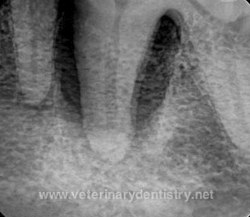

Before the cleaning, but after the dog is placed under anesthesia, a full-mouth set of x-rays should be obtained. Only x-rays below the gum lines will show the extent of damage to the roots of the teeth and any bone loss. For example, the black areas around the roots of the teeth in this x-ray (right) are hollow from bone loss due to periodontal disease.